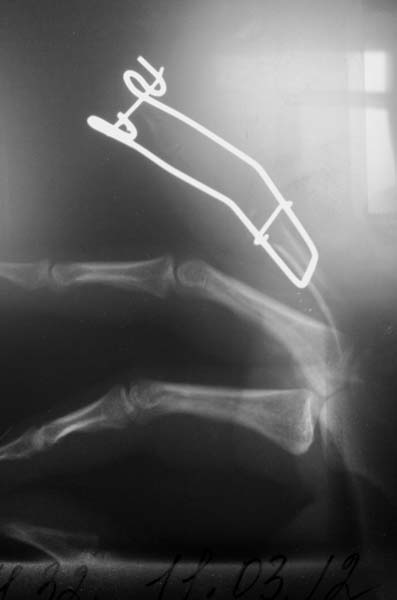

после первой операции

через 6 месяцев после первой операции

На данных R- граммах отсутствует практически вся средняя фаланга за исключением головки.

плохое качество снимков